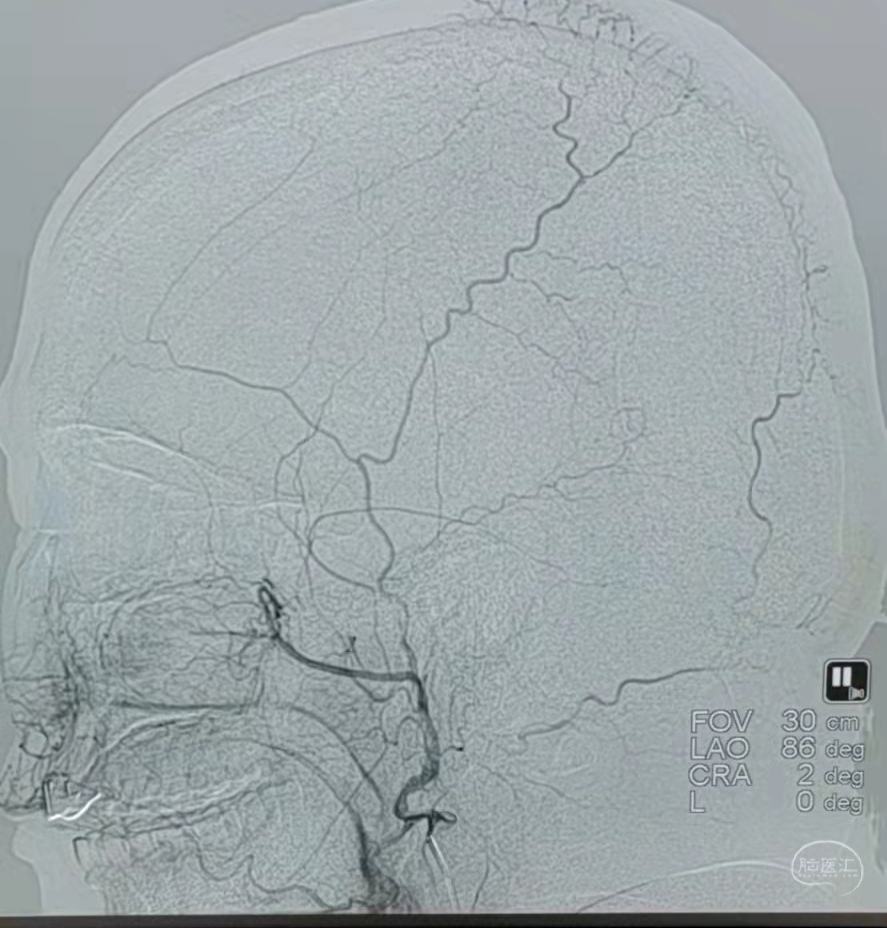

DSA:左侧颈内动脉闭塞。

颞浅动脉未向颅内代偿。

DSA:右侧大脑中动脉、大脑前动脉闭塞,烟雾样血管形成。

颞浅动脉未向颅内代偿。

DSA:左侧大脑中动脉、大脑前动脉闭塞,烟雾样血管形成。

颞浅动脉未向颅内代偿。

DSA:右侧大脑中动脉、大脑前动脉闭塞,烟雾样血管形成。

颞浅动脉未向颅内代偿。

DSA:左侧大脑中动脉、大脑前动脉闭塞,烟雾样血管形成。

颞浅动脉未向颅内代偿。